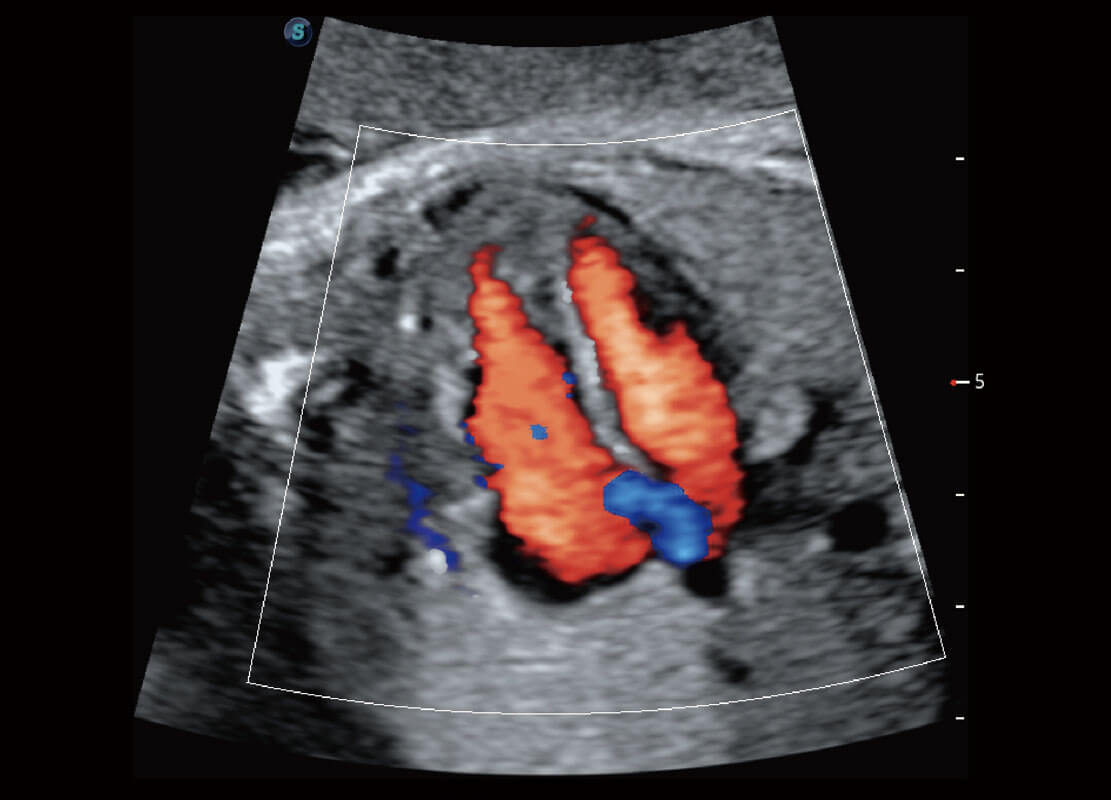

胎儿体循环

四腔心血流